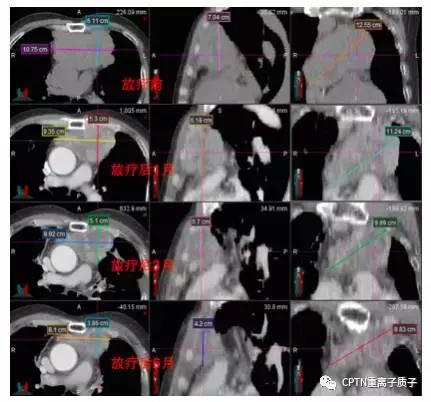

例:

不典型类癌患者,因高龄(74岁)、肿瘤巨大(11*8cm),手术风险大而拒绝手术治疗,且这类肿瘤通常对常规光子放疗和化疗均不敏感。患者接受根治性质子重离子放疗。肿瘤在放疗结束后1-9个月间持续缩小,放疗结束后15月最后一次复查时仍维持肿瘤受控态势。治疗不良反应包括轻度恶心、放射性肺炎和窦性心动过速等,放疗后3月内均明显缓解。